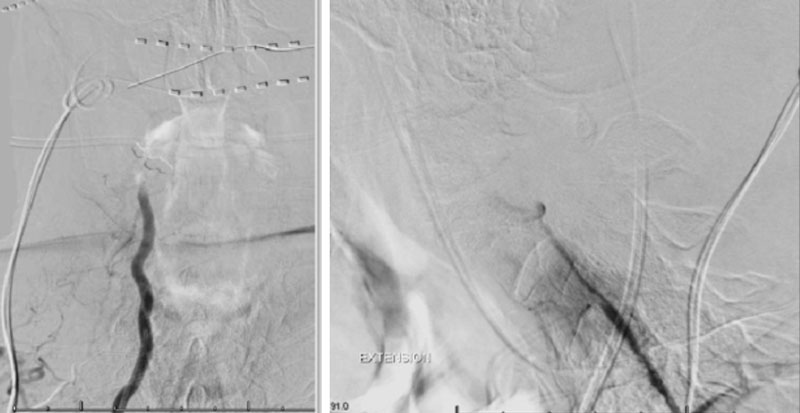

CTA of the neck and brain reveal that the left Vertebral Artery is completely occluded at approximately the C1-C2 level with extensive hypertrophic degenerative osseous changes from C1-C3. Retrograde flow into the post PICA left Vertebral Artery is observed from the co-dominant right Vertebral Artery which appears to be the primary supply into the basilar circulation. No significant Posterior Communicating arteries are observed on either the right or left Carotid Artery on the CTA imaging (Figure 1).

Dynamic provocative fluoroscopy failed to reveal significant Vertebral osseous instability (Figure 2A), however, Transcranial Doppler Flow velocities in the distal right Vertebral and Basilar Artery are markedly reduced during Extension of the Neck (Figure 2B).

We performed conventional catheter angiography with provocative testing to reproduce his symptoms. The right Vertebral Artery is the codominant primary supply to the basilar circulation with reflux into the distal left Vertebral Artery that is occluded (Figure 3).